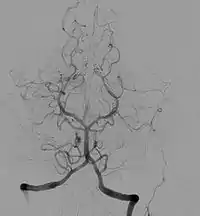

- Cerebral angiography

Subarachnoid hemorrhage (SAH) is bleeding into the cerebrospinal fluid (CSF) surrounding the brain. The two most common causes of SAH are rupture of aneurysms and bleeding from vascular malformations. Bleeding into the CSF from a ruptured aneurysm occurs very quickly, causing rapidly increased intracranial pressure. The initial bleed can be brief, but rebleeding is common. Death or deep coma ensues if the bleeding continues. SAH has a 37-45% mortality for patients 45 and older.[7][8]Cerebral aneurysms can be associated with other disorders, such as adult polycystic kidney disease.